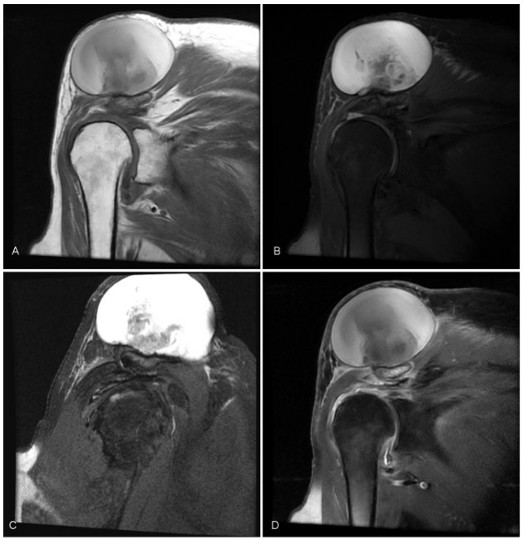

Presentamos dos casos a los que se les realizó una resonancia magnética (RM) con diagnóstico probable de quiste acromioclavicular. El primero, se trataba de una paciente de 77 años del sexo femenino, con una tumoración de hombro derecho, indolora, de un año de evolución. La radiografia mostró una tumoración de partes blandas, superior a la articulación acromioclavicular (AC), bien delimitada, sin lesiones óseas (Fig. 1). La RM mostró una formación quística, superior y en contacto con la articulación AC, sin realce con el contraste, de 86 mm de diámetro, bien delimitada, hiperintensa en secuencias ponderadas en T1 (alto contenido proteico) e hiperintensa en densidad protónica con saturación grasa (DPFS). Ademas, se observó una rotura completa del tendón del supraespinoso (Fig. 2).

Resonancia magnética (RM) de hombro derecho, (A) coronal en secuencias ponderadas en T1, (B) coronal DPFS (densidad protónica con supresión grasa), (C) sagital DPFS, (D) secuencia en plano coronal ponderada enT1 supresión grasa con contraste. Quiste acromioclavicular con elevada concentración proteica, hiperintenso en secuencias ponderadas en T1 y T2, sin realce poscontraste. Rotura de espesor completo del tendón del supraespinoso.